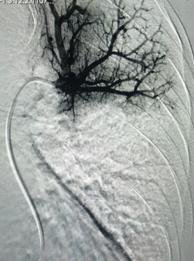

經(jīng)皮肺動脈造影

經(jīng)綜合評估并與家屬充分溝通后,局麻下行肺動脈造影,提示左肺動脈主干及左肺下葉動脈閉塞,立即予以經(jīng)皮肺動脈栓塞導管介入碎栓溶栓術(shù)。在心內(nèi)科韋鋒主任、郭良玉主治醫(yī)師及成婷護師的默契配合下,爭分奪秒順利完成手術(shù)。術(shù)后即刻復查肺動脈造影示左肺動脈主干及左肺下葉動脈恢復血流,生命體征穩(wěn)定,指脈氧恢復至100%。經(jīng)過精心治療與護理,目前患者已康復出院。